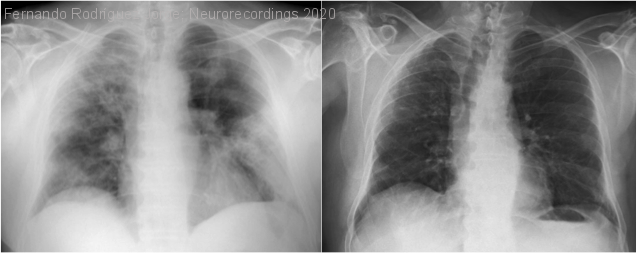

Resumen del caso

Antecedentes: dislipemia. Ingresa en planta de Medicina Interna con diagnóstico de neumonía bilateral por SARS-CoV-2, iniciándose tratamiento con ceftriaxona, hidroxicloroquina y lopinavir/ritonavir. Al tercer día de ingreso, coincidiendo con empeoramiento respiratorio y radiológico, presentó cuadro...